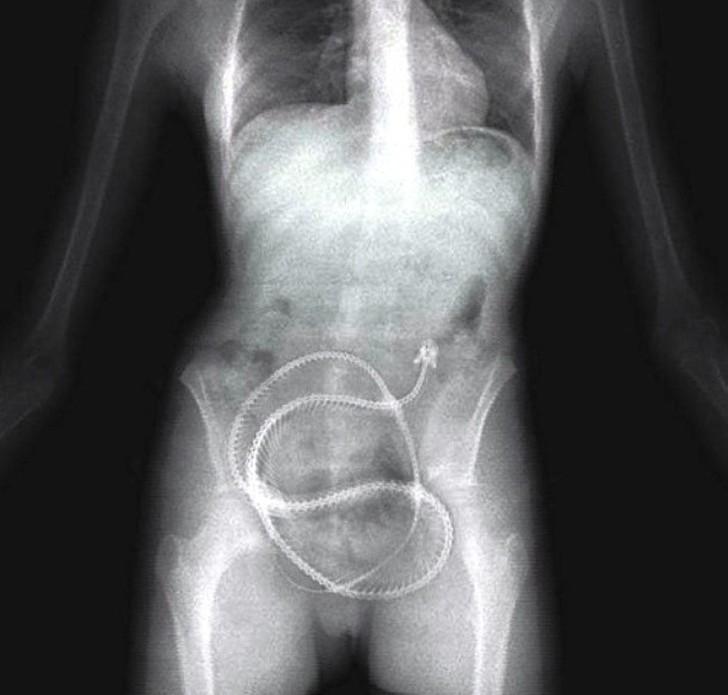

22. Хирургические щипцы.